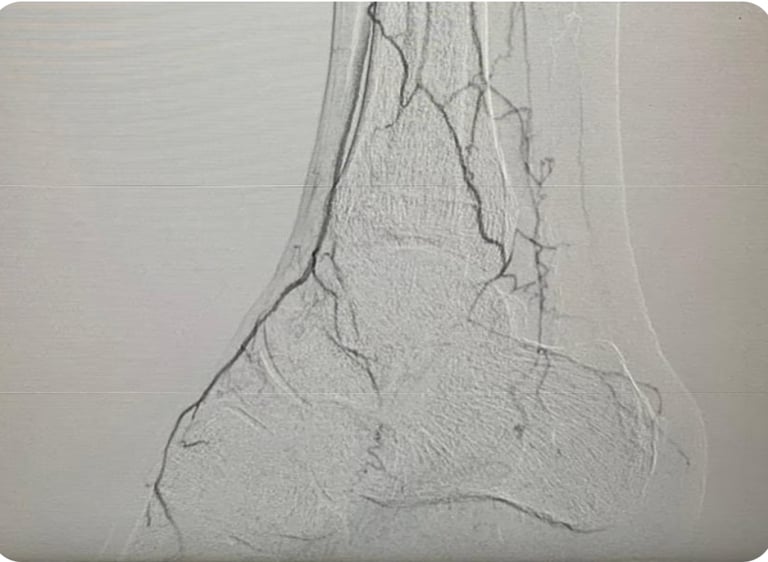

Tratamientos avanzados para problemas arteriales y venosos con cirugía abierta

Diagnóstico y tratamiento de enfermedades como pie diabético, enfermedad arterial periférica, enfermedad carótida, aneurismas y enfermedad venosa

Endovascular

Intervenciones mínimamente invasivas para salud vascular óptima.